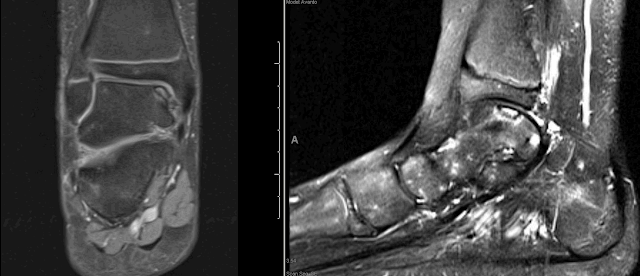

Ankle Osteochondral Defects / OCD

I have attached imaging of some recent osteochondral lesions that have been treated at our hospital.